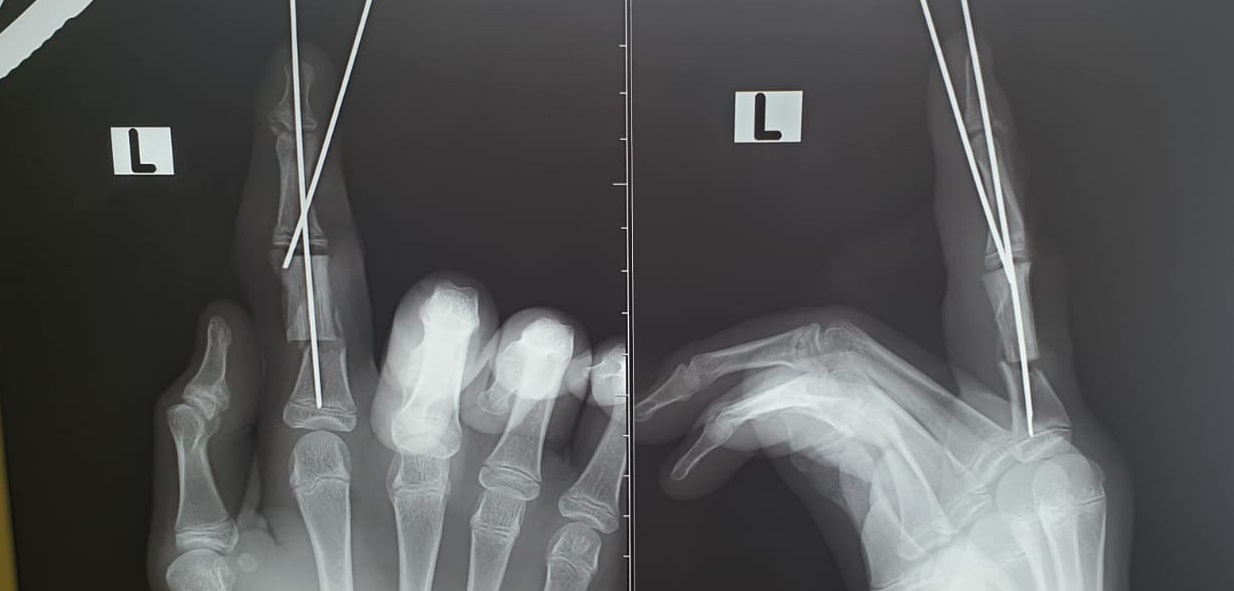

Как сообщили врачи, ребёнок работал на дачном участке и повредил «болгаркой» пальцы левой руки. Пострадавший обратился в травмпункт, откуда его направили в клинику Педиатрического университета.

- Мы диагностировали неполную  травматическую ампутацию указательного пальца и скальпированные раны среднего пальца. Половина основной фаланги указательного пальца отсутствовала, она  была размозжена. Палец держался на сосудисто-нервных пучках. Нам нечем было закрывать большой дефект кости, речь шла либо об укорочении пальца, либо о замещении поврежденного участка собственным фрагментом кости пациента - так называемой аутотрансплантации , - сообщил детский хирург Михаил Азаров

Операция продлилась более трёх часов и завершилась успешно. Мальчик продолжает лечение в клиники вуза.

- Важно понимать, что,  так как пациент травмировал суставную поверхность, ему потребуется длительная реабилитация, и могут быть ограничения в подвижности пальца, - сообщил Михаил Азаров.